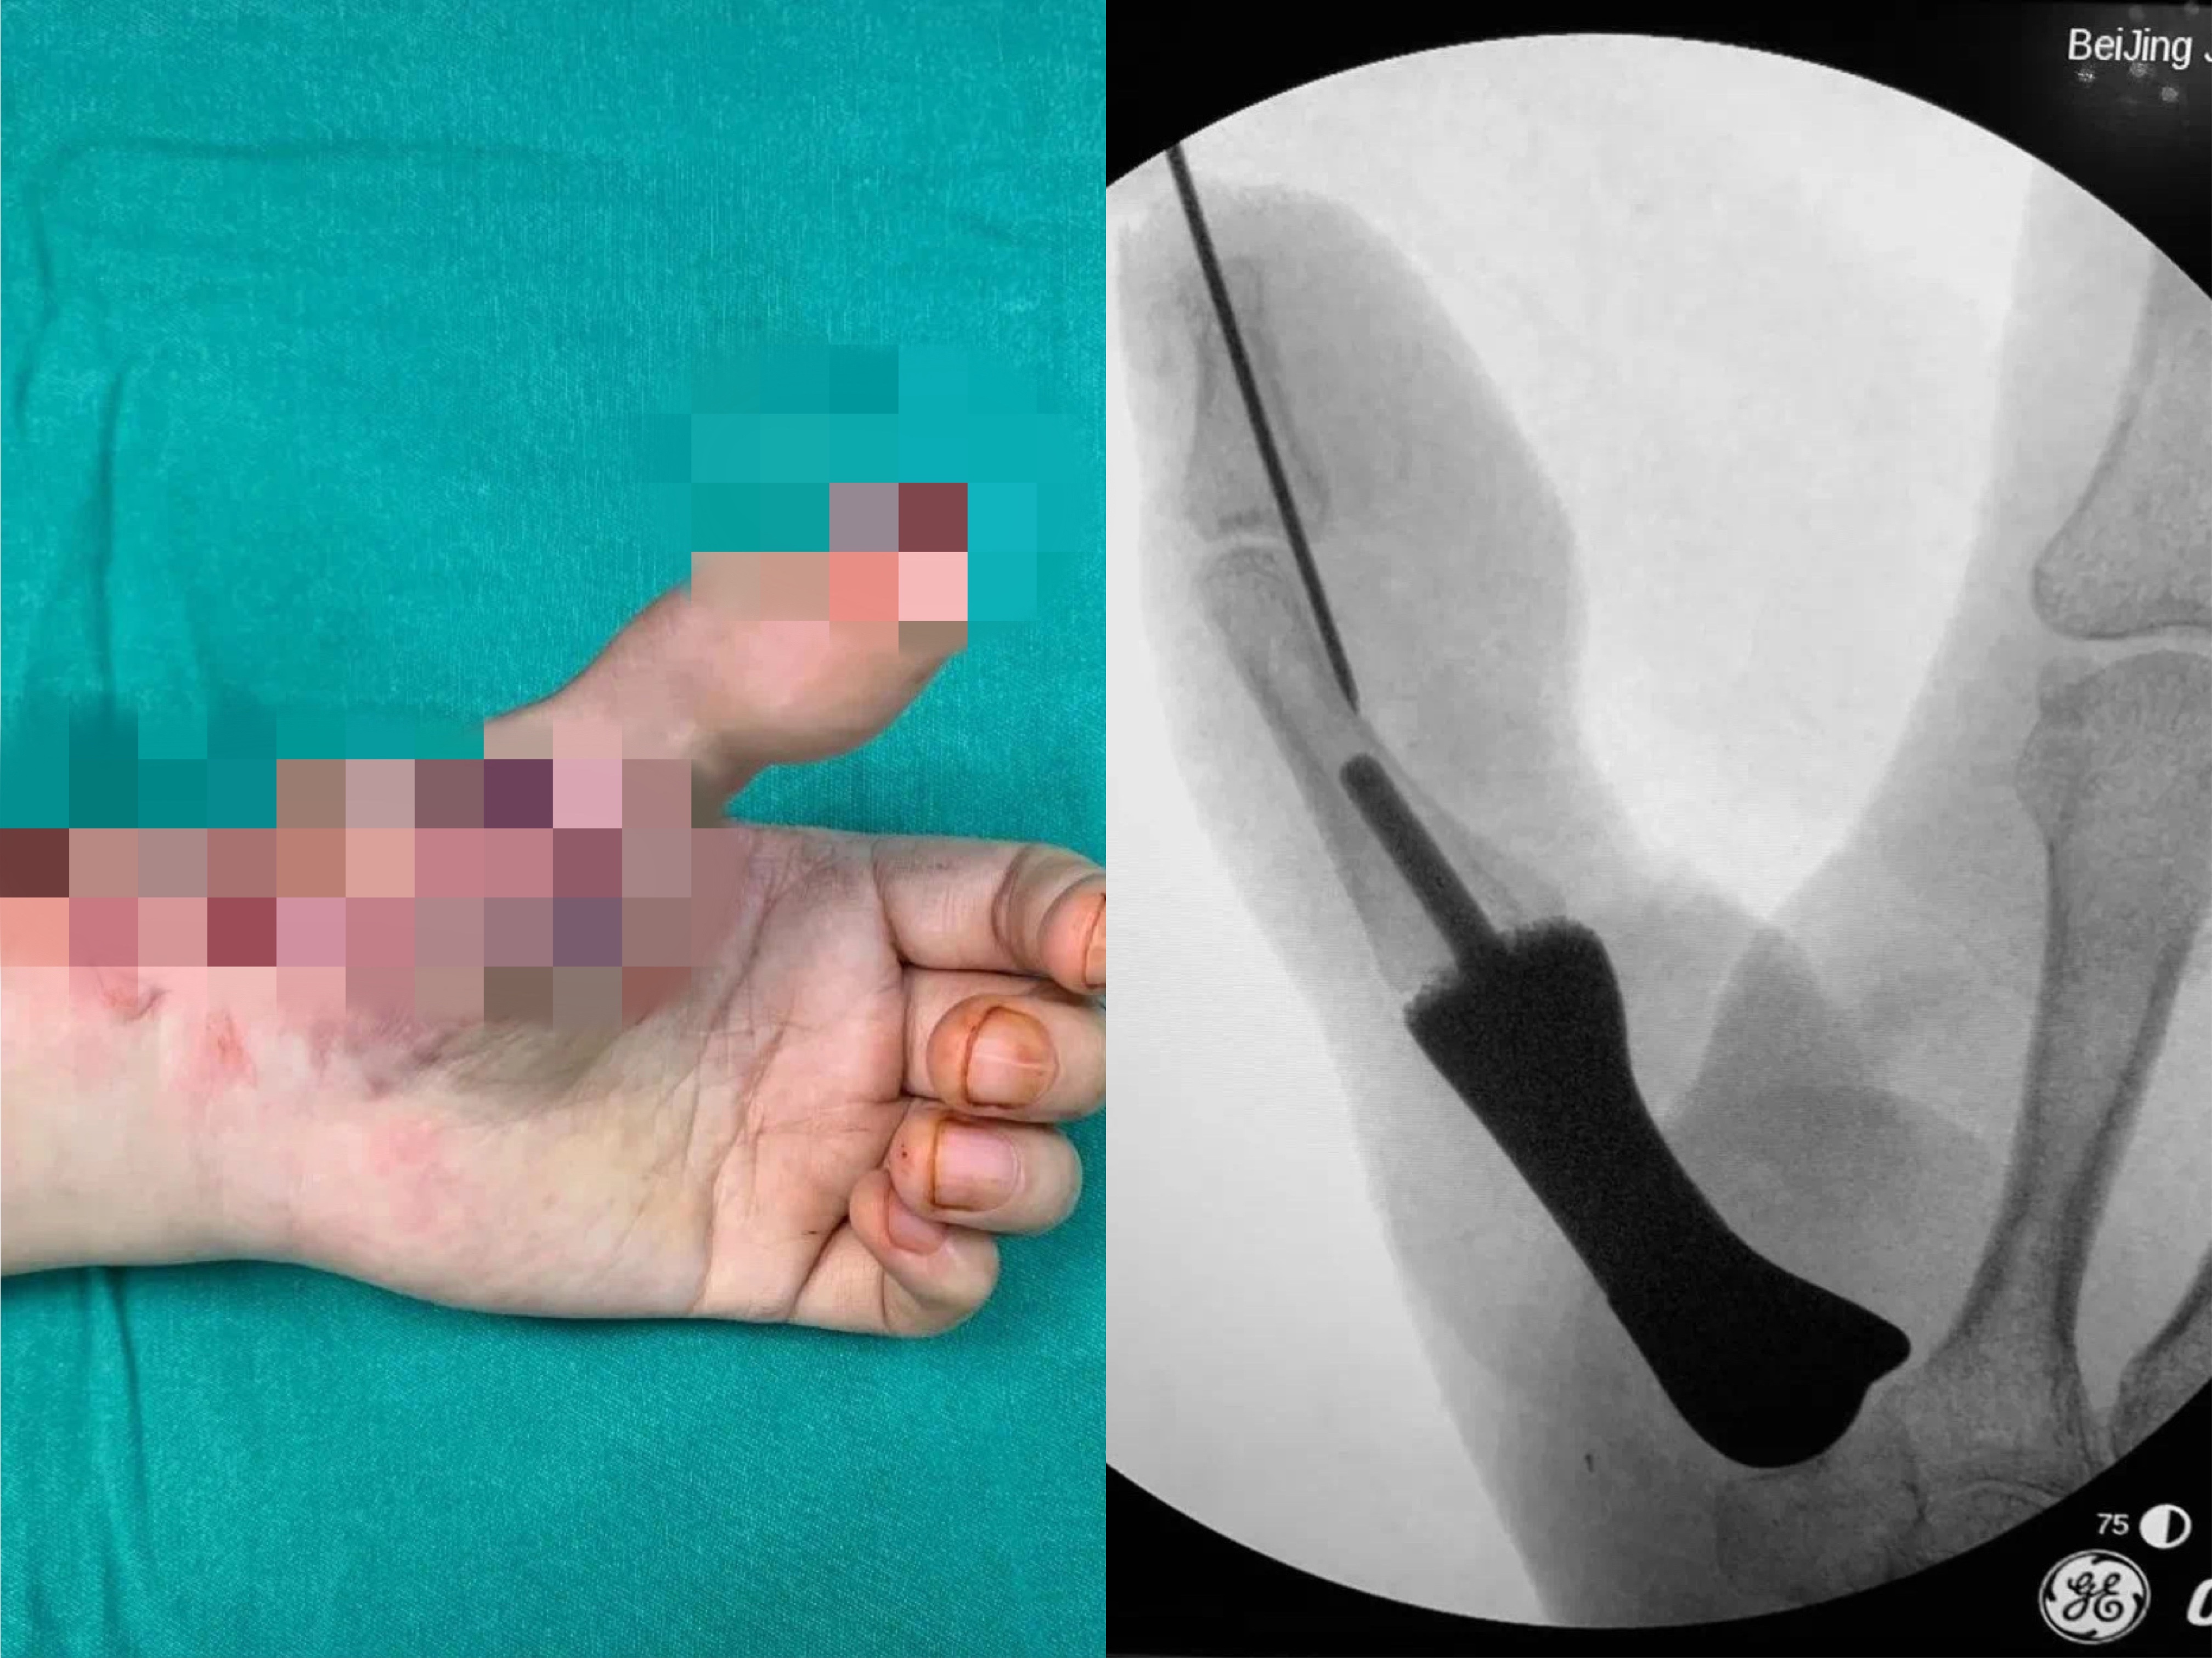

据介绍,患者因机器伤导致左手拇指在掌骨水平近端离断,在外院进行了再植术,但术后手指存活情况欠佳。随后又做了多次手术,但都没有成功保指。患者左手拇指仅残留部分冗余皮肤,没有掌骨,外观和功能都受到极大影响。

图为患者术前手部影像。(北京积水潭医院供图)

北京积水潭医院手外科主任陈山林检查后发现,患者左手第一系列缺失,若采用传统方法进行拇指再造,不仅重建的掌骨有被吸收掉的风险,而且患者无法获得有功能的腕掌关节,然而稳定且可活动的腕掌关节恰恰在发挥拇指功能中是最为重要的一环。考虑到患者左手仍保留完整的大多角骨,陈山林团队决定为患者定制化制作金属3D打印的第一掌骨,满足患者第一腕掌关节的解剖学重建,为患者的拇指再造提供一个良好的骨性基础。